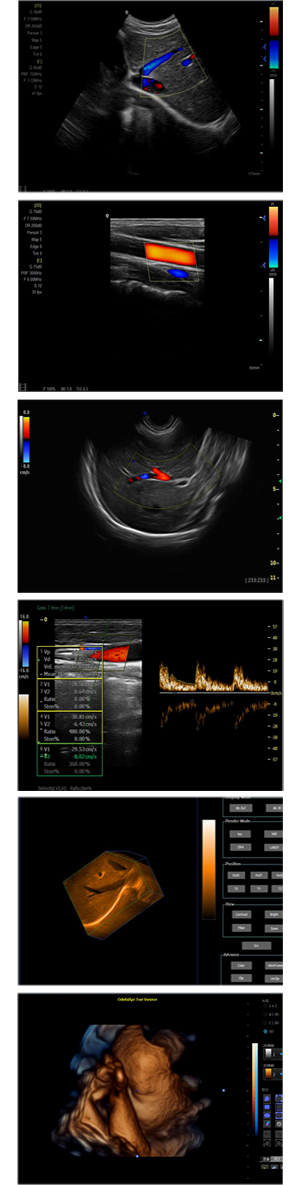

XF-7600型,秉承先鋒彩超技術(shù)之精華,擁有高雅大氣的獨(dú)特外型,為最新一代應(yīng)用型數(shù)字彩色多普勒診斷系統(tǒng),魅力與實(shí)力相融合??蓮V泛適用于腹部、婦產(chǎn)科、心臟、小器官、乳腺、肌骨及外周血管等諸多方面的診查,讓您在臨床超聲診斷應(yīng)用領(lǐng)域得心應(yīng)手,綻放異彩!

突破的成像技術(shù)

● 3D/ 4D成像技術(shù)/選配

● 應(yīng)用于腹部、腎臟、泌尿系統(tǒng)、產(chǎn)科、婦科、盆腔、大動(dòng)脈、肌肉組織、小器官、乳腺、心臟等

● 能量多普勒成像(PDI)

● 彩色血流量圖(CDE)

● 脈沖頻譜多普勒成像(PW)